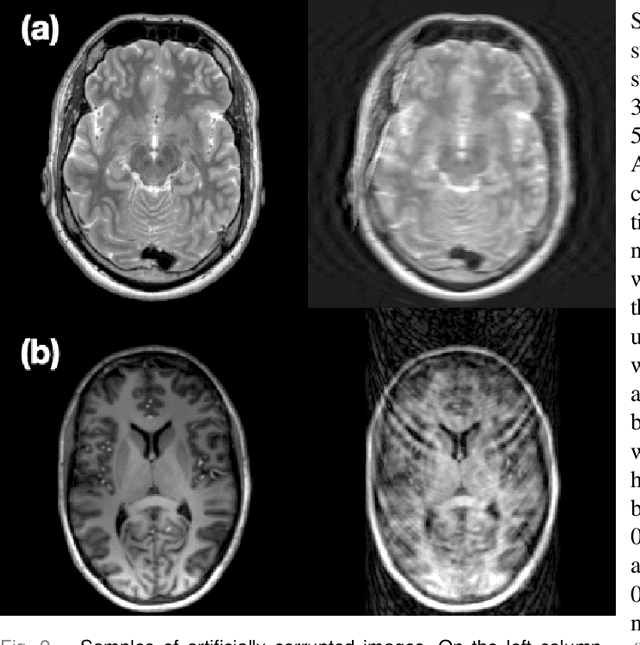

Abstract:Motion artefacts in magnetic resonance brain images are a crucial issue. The assessment of MR image quality is fundamental before proceeding with the clinical diagnosis. If the motion artefacts alter a correct delineation of structure and substructures of the brain, lesions, tumours and so on, the patients need to be re-scanned. Otherwise, neuro-radiologists could report an inaccurate or incorrect diagnosis. The first step right after scanning a patient is the "\textit{image quality assessment}" in order to decide if the acquired images are diagnostically acceptable. An automated image quality assessment based on the structural similarity index (SSIM) regression through a residual neural network has been proposed here, with the possibility to perform also the classification in different groups - by subdividing with SSIM ranges. This method predicts SSIM values of an input image in the absence of a reference ground truth image. The networks were able to detect motion artefacts, and the best performance for the regression and classification task has always been achieved with ResNet-18 with contrast augmentation. Mean and standard deviation of residuals' distribution were $\mu=-0.0009$ and $\sigma=0.0139$, respectively. Whilst for the classification task in 3, 5 and 10 classes, the best accuracies were 97, 95 and 89\%, respectively. The obtained results show that the proposed method could be a tool in supporting neuro-radiologists and radiographers in evaluating the image quality before the diagnosis.